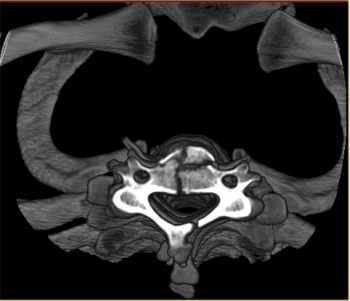

CT Scan

CT scans or computerized tomography integrate several X-ray images to create more detailed cross-sections. It is a simple non-invasive procedure that enables medical professionals to obtain diagnostic information on the brain, chest, abdomen, pelvis, spine and extremities.